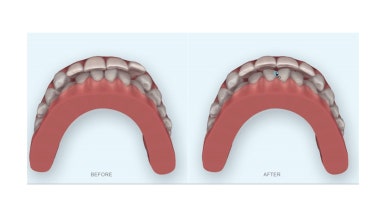

연산동부분교정 치료에 앞서 시뮬레이션 해서 보여드렸습니다.

공간 부족으로 앞니가 튀어나간거니 해당 치아를 쏙 밀어 넣으려면 다른 치아도 약간씩 움직여 줘야 하고 위아래 앞니가 더 긴밀해지거나 중심선이 약간 트어져 보일 수 있는 점, 기타 등등 마이너스가 될 수 있는 부분들 충분히 설명 드리고 진행하게 되었습니다.